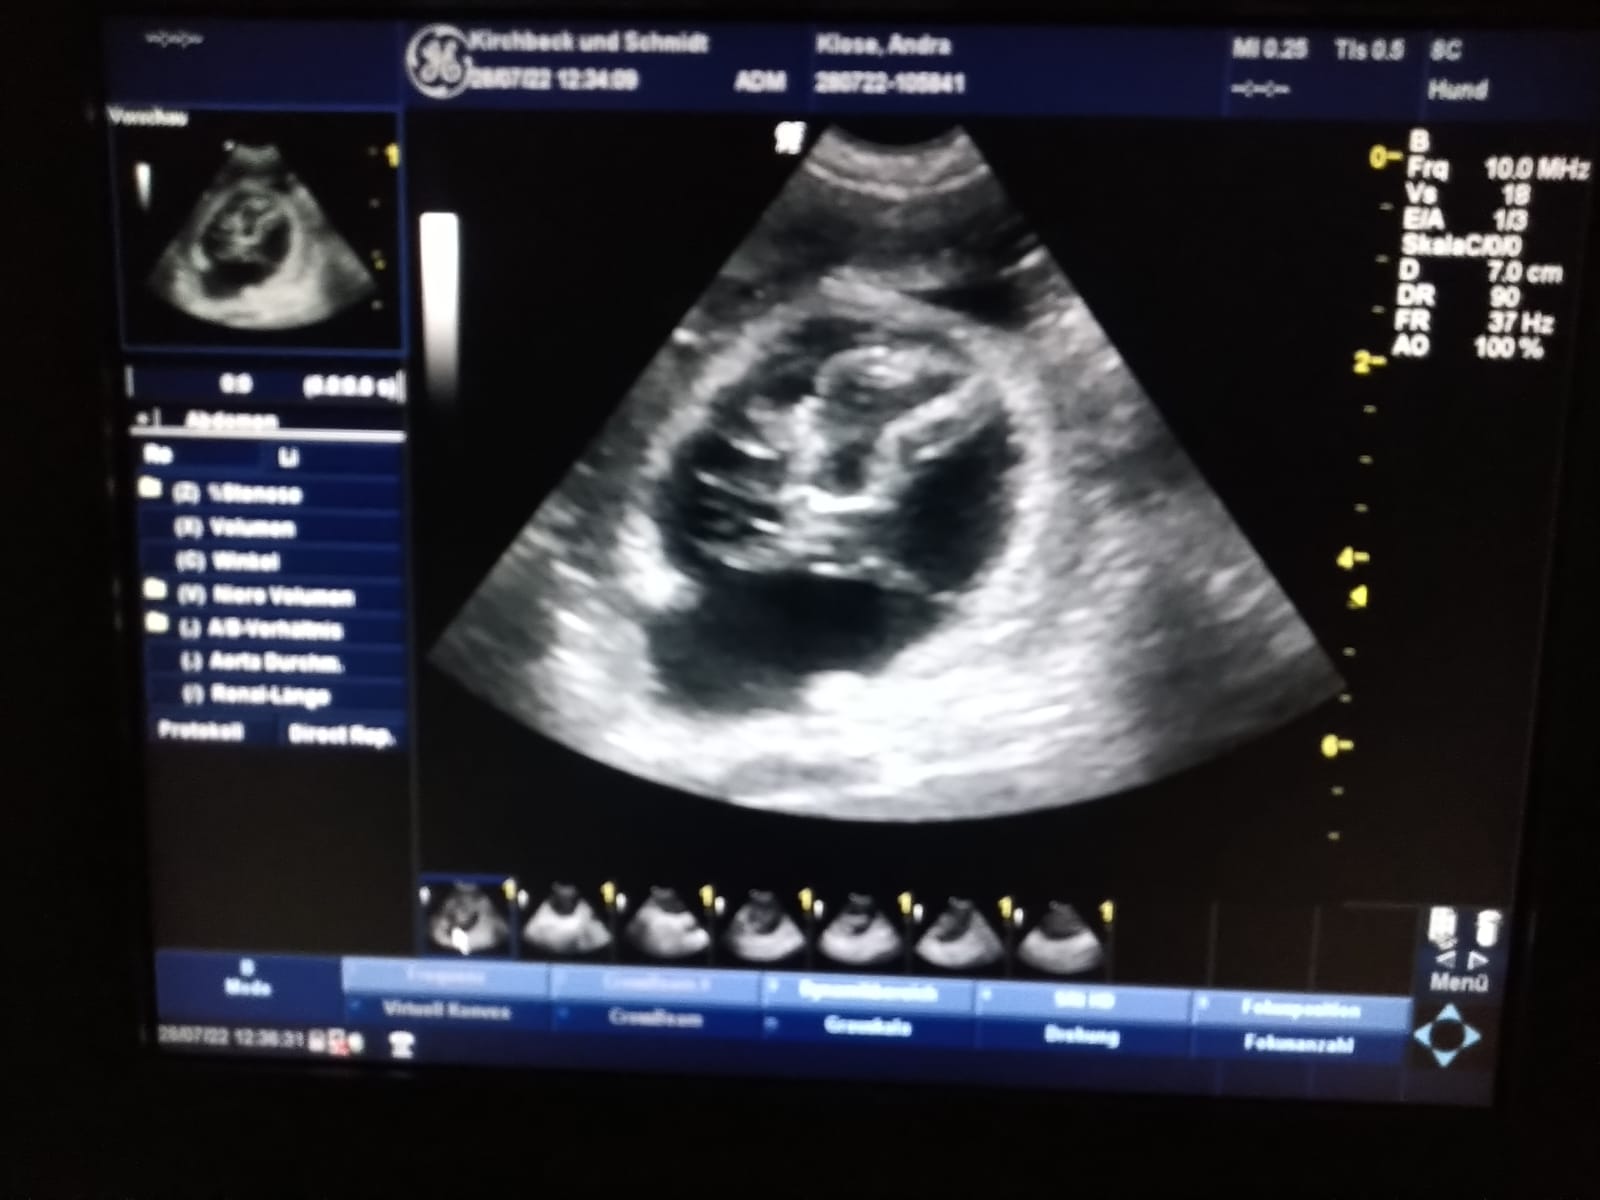

Seit Dezember 2022 ist Aiven als Deckrüde in der HZD gelistet. Jetzt hatte er seinen ersten Einsatz... und es hat auf Anhieb geklappt. Wir sind total stolz auf Aiven!! Er hatte Besuch von Ambra vom Rissgarten, gen Ellie. Beide unerfahren, aber dennoch instinktsicher. Jetzt drücken wir ganz doll die Daumen das die beiden den A-Wurf vom Heckengäu auf den Weg gebracht haben und wünschen Katrin und ihrer Hündin eine gut gefüllte Schnullerbox mit tollen gesunden Welpen! Aber wie wir als Züchter ja wissen, jetzt heißt es erst einmal wieder warten... auf den Ultraschall Anfang Februar 2024! ... weitere Bilder findet ihr auf Aivens Seite